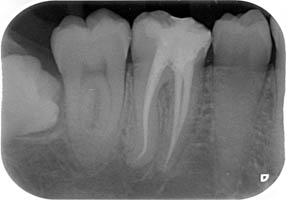

La endodòncia és la part de la odontologia que tracta la pulpa dental (o nervi de les dents). Aquesta pulpa està localitzada en un sistema de conductes radiculars que tenen les dents.

La majoria de vegades, les patologies que afecten la pulpa dental són produides per grans càries. Quan això succeeix, es produeix una inflamació o necrosis del teixit de la pulpa dental, i és necessària la extirpació d'aquesta. Això requereix un desbridament i conformació d'aquests conductes, i una obturació o segell dels mateixos amb materials biocompatibles. Això és el que es coneix com una endodòncia, o vulgarment dit, "matar el nervi".

Aquest tractaments és complexe. Normalment, es pot realitzar en una visita, tot i que de vegades es necessitin més segons la complexitat del cas (nombre d'arrels del queixal, corvatura i longitut, de les mateixes, calcificacions de la pulpa, etc.)